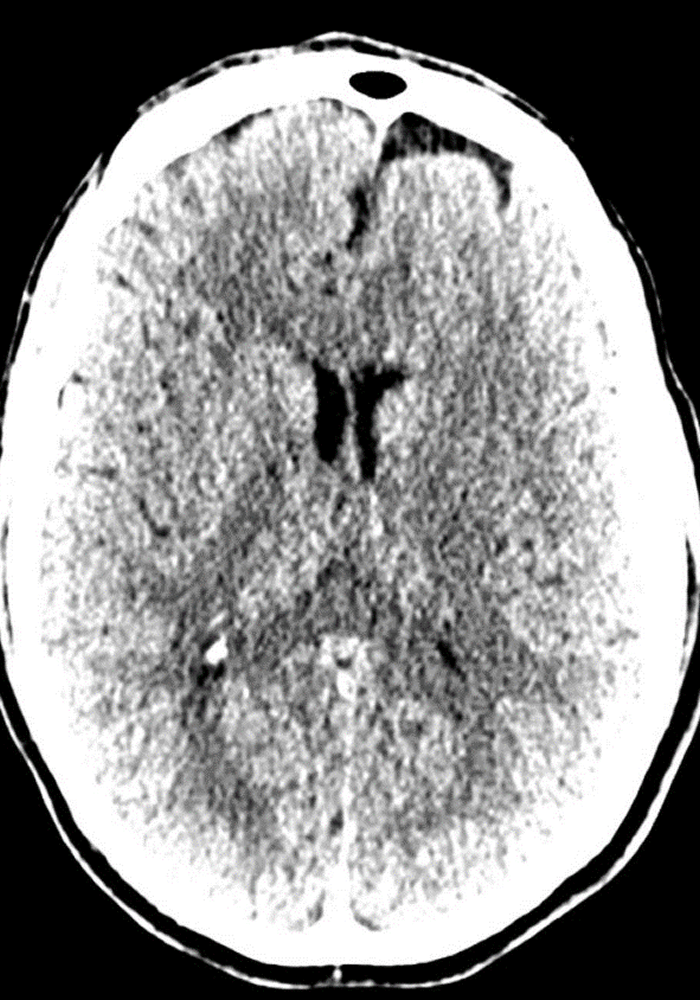

radiology

Vessel and Brain tumor segmentation

Before: "fuzzy" head CT

datascientists after

After: detailed images

Our V Star computer scientists wrote a module for 3D-Slicer allowing careful alignment and summation from 8 prior CT scans obtained over a course of several years. This improved image contrast resolution without loss of spatial resolution